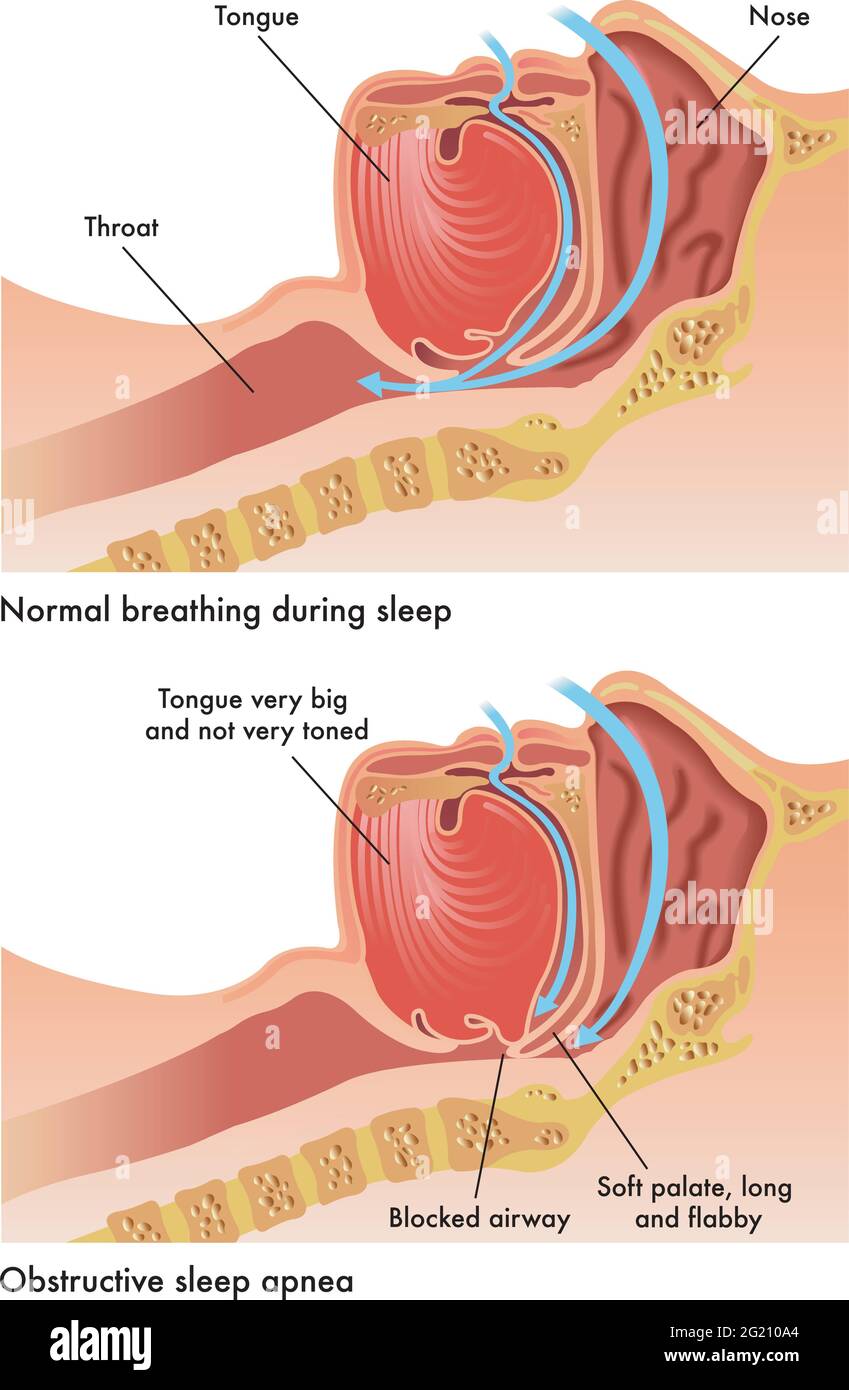

Medical illustration of the consequences of obstructive sleep apnea. Stock Vectorhttps://www.alamy.com/image-license-details/?v=1https://www.alamy.com/medical-illustration-of-the-consequences-of-obstructive-sleep-apnea-image431510748.html

Medical illustration of the consequences of obstructive sleep apnea. Stock Vectorhttps://www.alamy.com/image-license-details/?v=1https://www.alamy.com/medical-illustration-of-the-consequences-of-obstructive-sleep-apnea-image431510748.htmlRF2G210A4–Medical illustration of the consequences of obstructive sleep apnea.